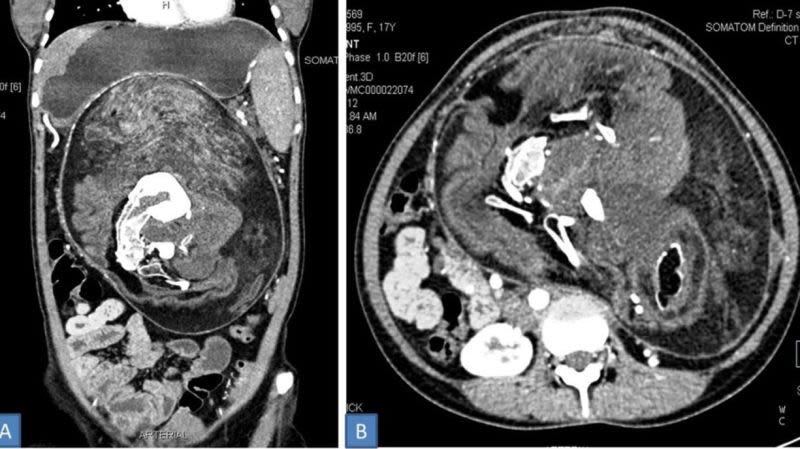

Acude a urgencias por un fuerte dolor de estómago y le encuentran los restos de su gemelo parcialmente formado

Los médicos no daban crédito a los resultados de los primeros análisis. Cuando una joven de 17 años en Patna, India, llegó a urgencias aquejada de un fuerte dolor en el estómago que había crecido hasta distorsionar su cavidad abdominal, los expertos parecían tenerlo claro: debía ser un tumor. Sin embargo, aquella masa tenía dientes.